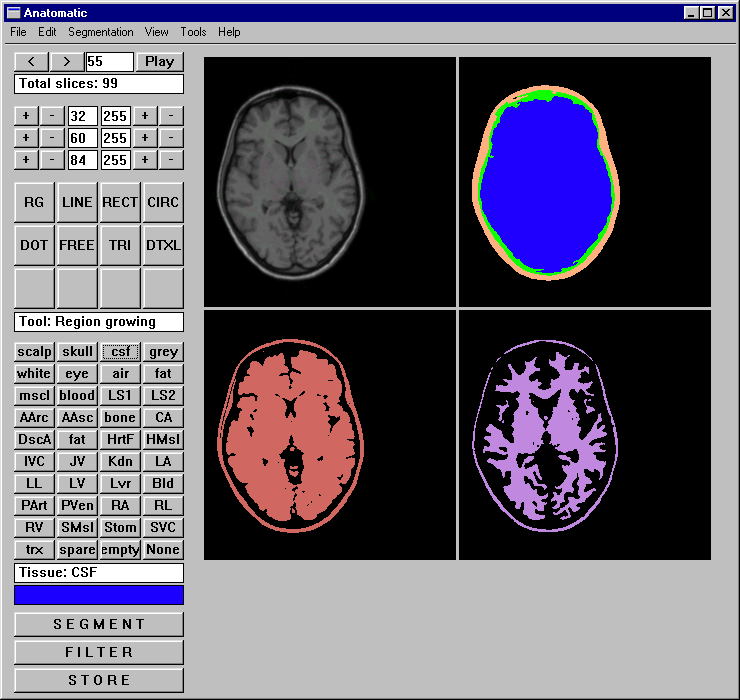

The user interface of Anatomatic appears similar to a bitmap drawing program and is presented in Fig 3. First

the segmentation technique (IARD, manual, reloading, and lesion tracking) is selected. Then an image stack of MR

or CT images is opened and displayed on the screen. Current slice is defined and appropriate threshold coefficients

are selected. Thereafter a segmentation tool and a color representing a tissue are selected and the images are

modified. After the result appears realistic the user stores the segmented data and begins to process the next

image. The above mentioned steps are repeated as many times as there are images in the data set. However, one image

can be processed as many times as required, e.g., when several tissues are detected. If the appearance of images

is too small the window can be zoomed.

Figure 3. The user interfaces of Anatomatic and Medimag software. Anatomatic can be applied

in various segmentation procedures and applies IARD algorithm. Medimag is capable in visualizing raw medical images

(applying thresholding) and segmented data.